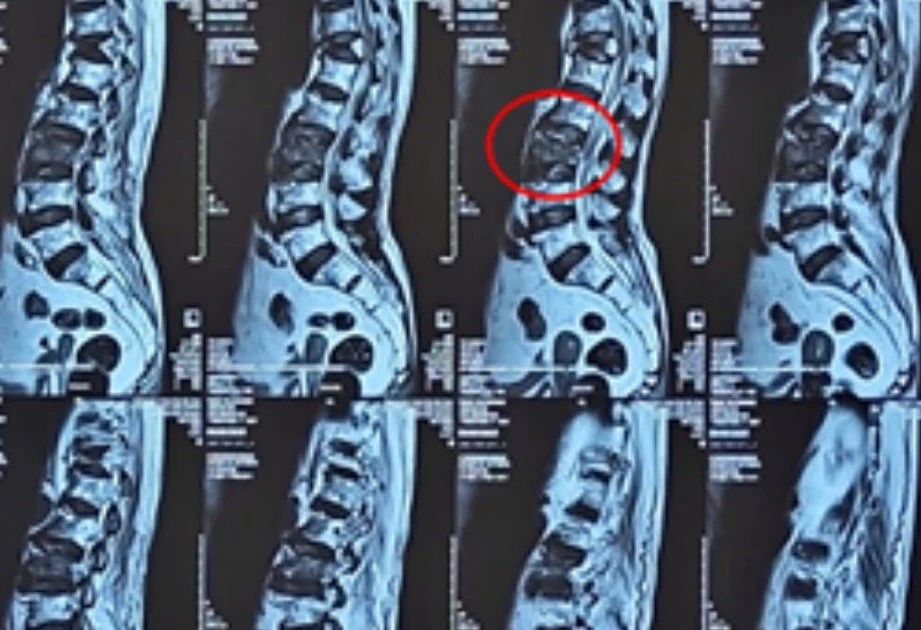

Bơm ‘xi măng’ vào đốt sống cứu cụ bà 100 tuổi

Cụ bà 100 tuổi thoát khỏi đau đớn và phục hồi vận động sau khi được bác sĩ bơm xi măng vào đốt sống bị gãy, loãng xương nặng.